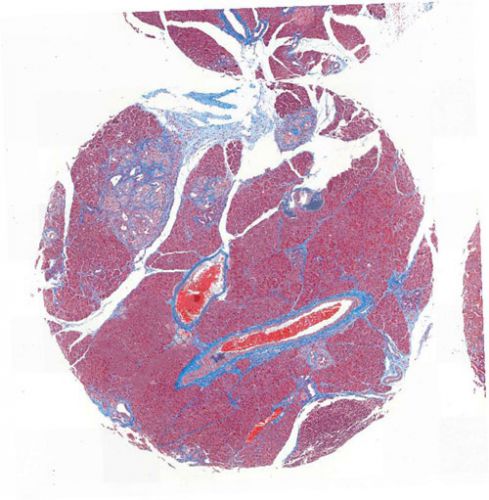

Masson,天狼猩紅,油紅O染色:分析陽性面積、組織面積以及陽性面積占比。

分析過程展示圖